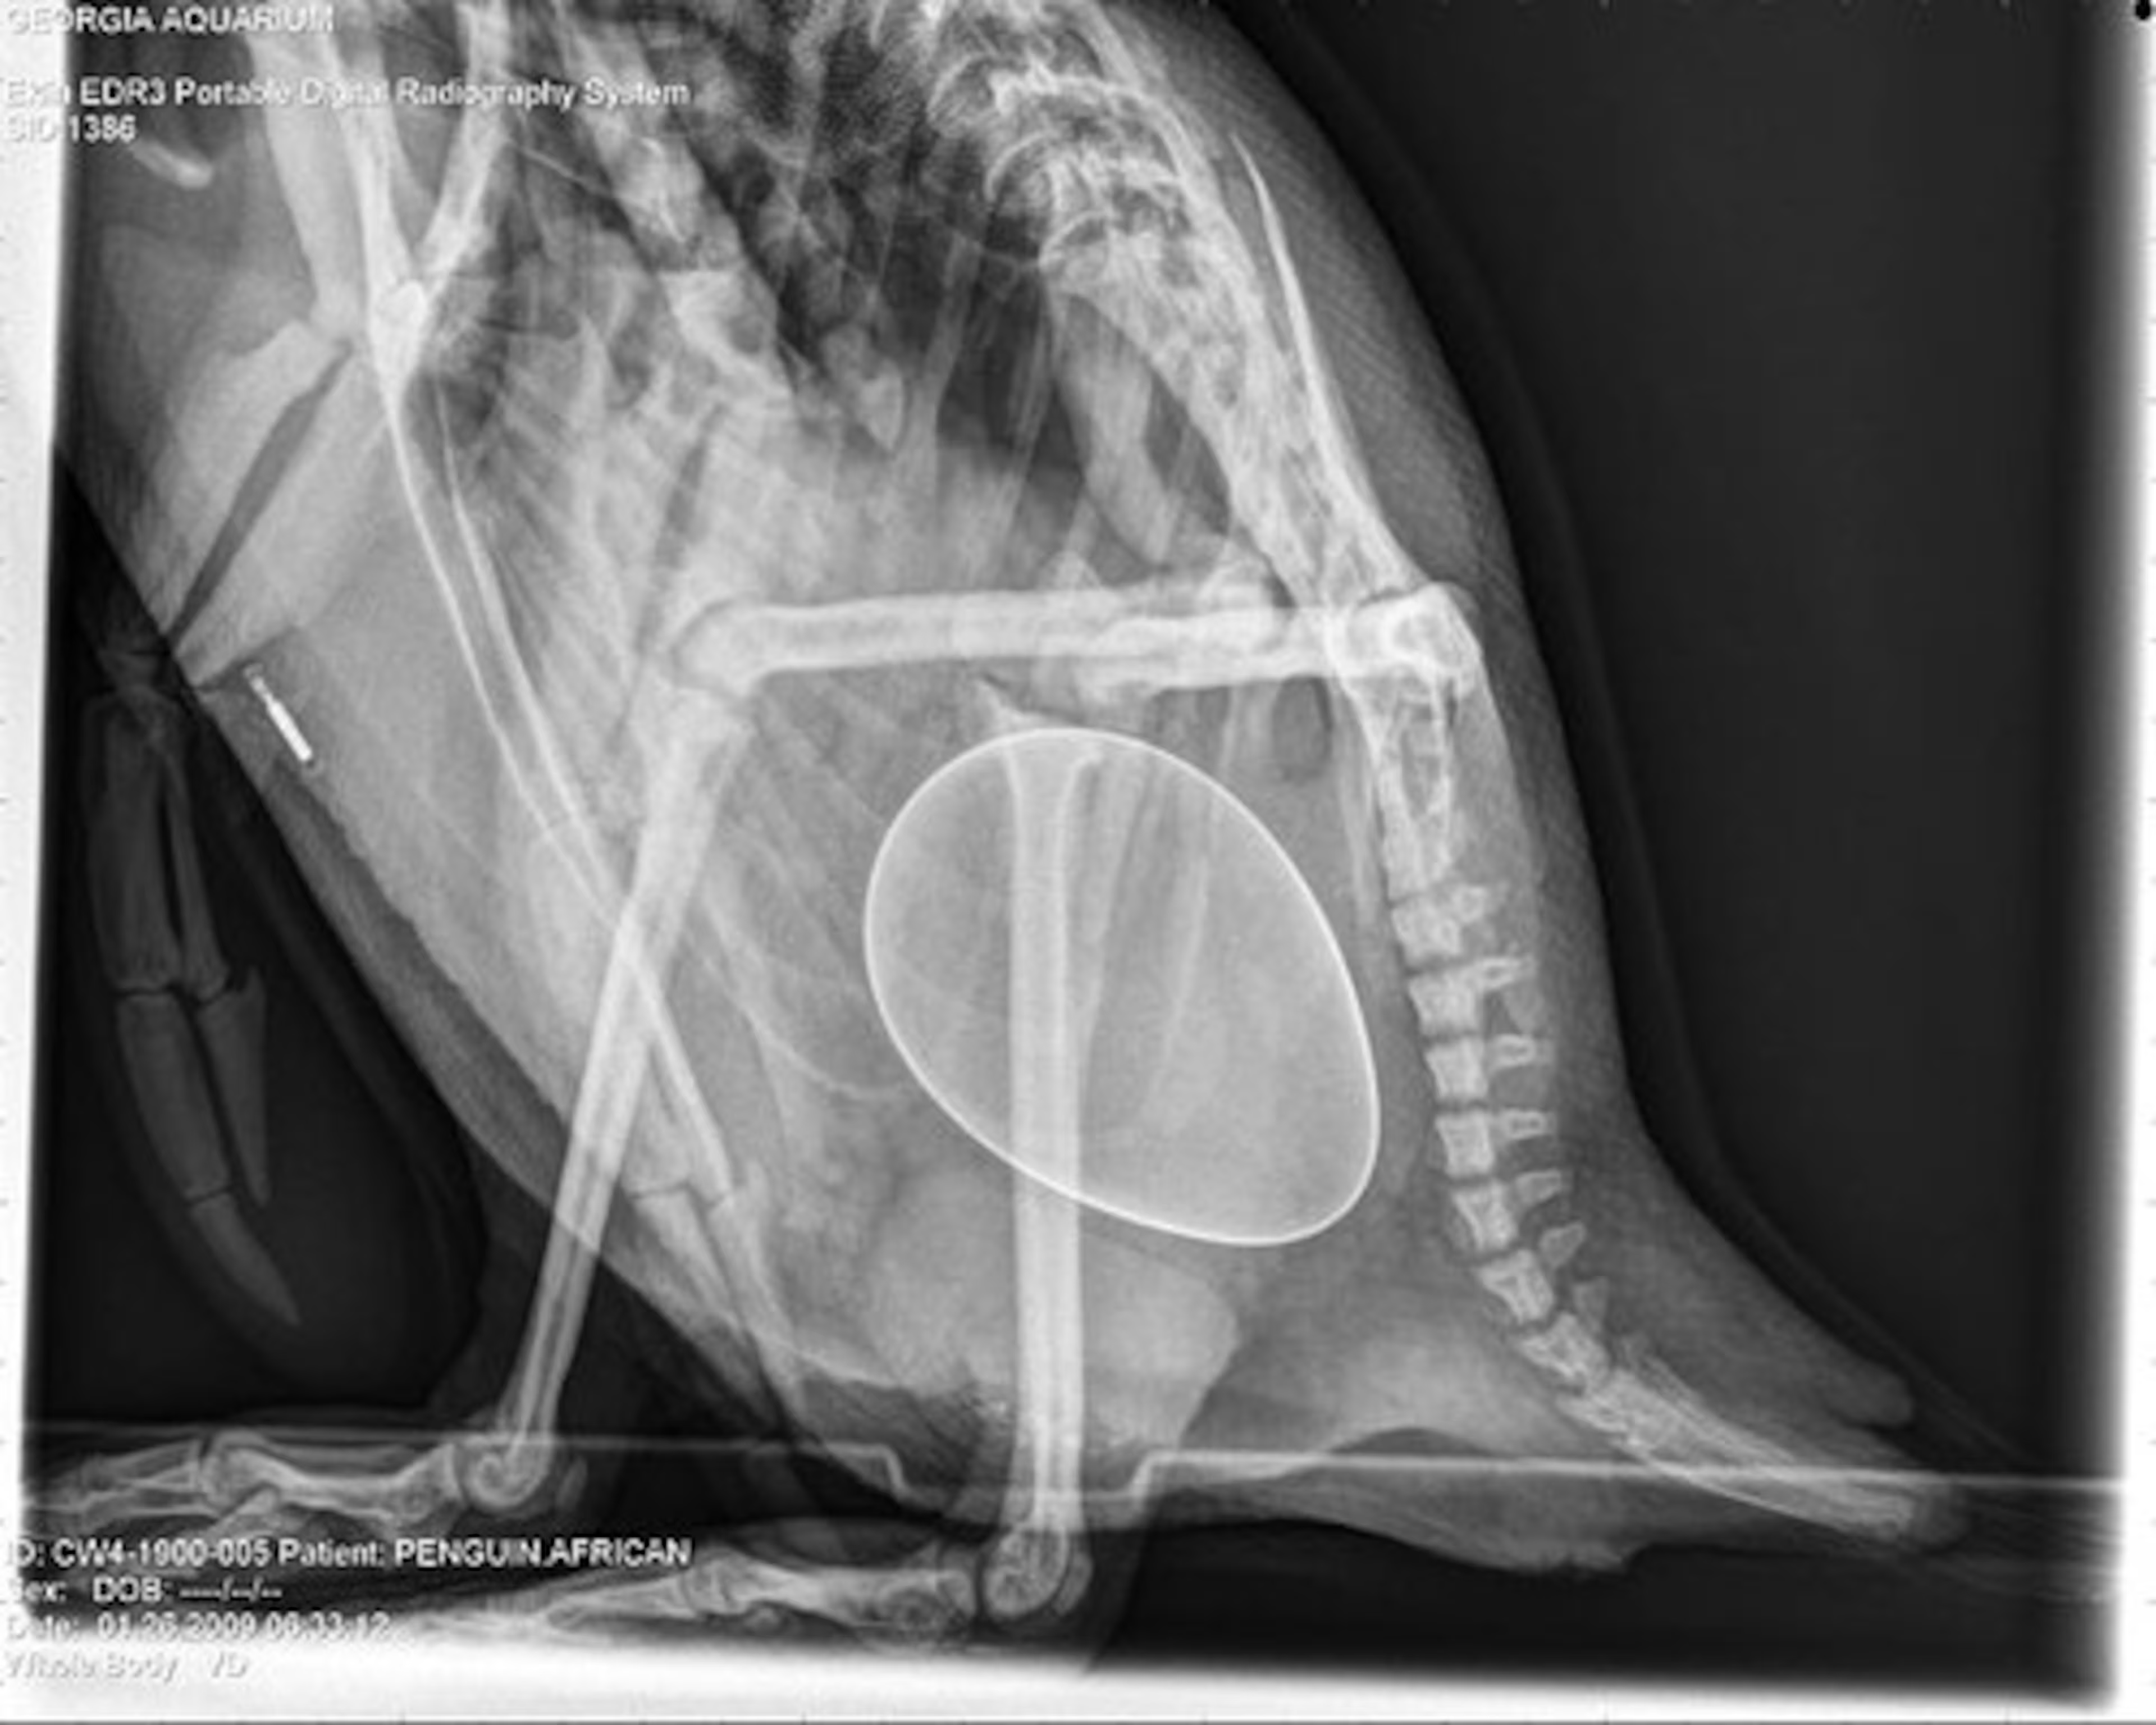

DEY DO WALLSITS, IT HAB PROOF